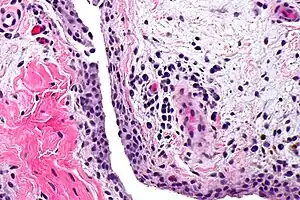

Synovitis

Synovitis is the medical term for inflammation of the synovial membrane. This membrane lines joints that possess cavities, known as synovial joints. The condition is usually painful, particularly when the joint is moved. The joint usually swells due to synovial fluid collection.

| Chronic synovitis | |

Synovitis may occur in association with arthritis as well as lupus, gout, and other conditions. Synovitis is more commonly found in rheumatoid arthritis than in other forms of arthritis, and can thus serve as a distinguishing factor, although it is also present in many joints affected with osteoarthritis.[1][2] In rheumatoid arthritis, the fibroblast-like synoviocytes, highly specialized mesenchymal cells found in the synovial membrane, play an active and prominent role in the synovitis.[3] Long term occurrence of synovitis can result in degeneration of the joint.